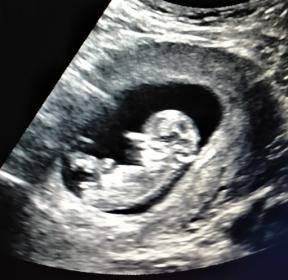

Attachment 43274

When in doubt get an elective ultrasound! I really got my 2nd daughter! I feel like I'm dreaming lol